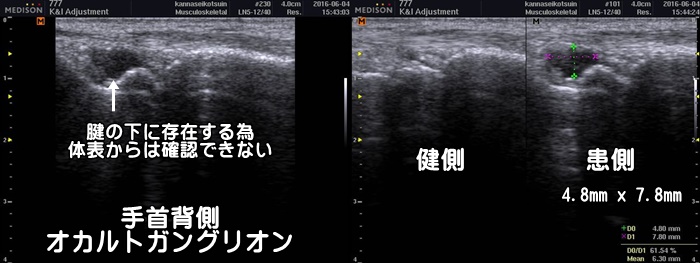

手首の甲のガングリオン

腕立て伏せのような形で手をつくと手首の甲側に痛みがある場合、ガングリオンが疑われます。ガングリオンは浅い所にできると体表からでも膨らみが確認できますが、上図の様に腱の下にできたオカルトガングリオンは体表からでは確認できません。レントゲンでは異常なしと言われます。通常ガングリオンは3年で約80%が自然消失します。